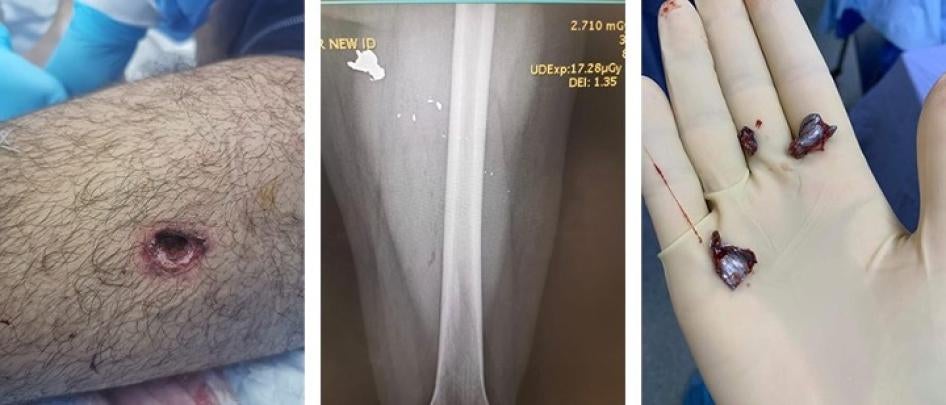

راجعت هيومن رايتس ووتش السجلّات الطبية لعمر في 8 أغسطس/آب، بما فيها صور الأشعّة السينية التي أظهرت ثلاث شظايا كبيرة من الرصاص وشظايا عديدة أصغر في رجله اليسرى. قال: "لحسن الحظ، لم تصل الرصاصة إلى عظمي. كانت قريبة من الشريان، لكنّها بالكاد لم تلامسه".

أطلقت القوات الأمنية رصاصة على عمر فأصابت أعلى فخذه الأيسر. الصورة على اليسار تظهر جرح دخول الرصاصة. تُظهر الأشعة السينية ثلاث شظايا رصاصة كبيرة وعدة شظايا أصغر في ساقه اليسرى، والصورة على اليمين تُظهر الشظايا المستخرجة من ساقه.  © 2020 تقدمة عمر